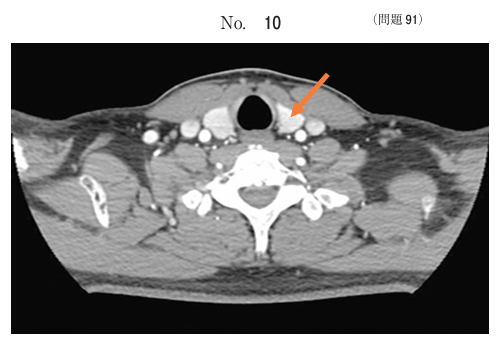

午前/問題91

頸部の造影CT像別冊No. 10 を別に示す。矢印で示すのはどれか。

1.気管

2.食道

3.甲状腺

4.総頸動脈

5.内頸静脈